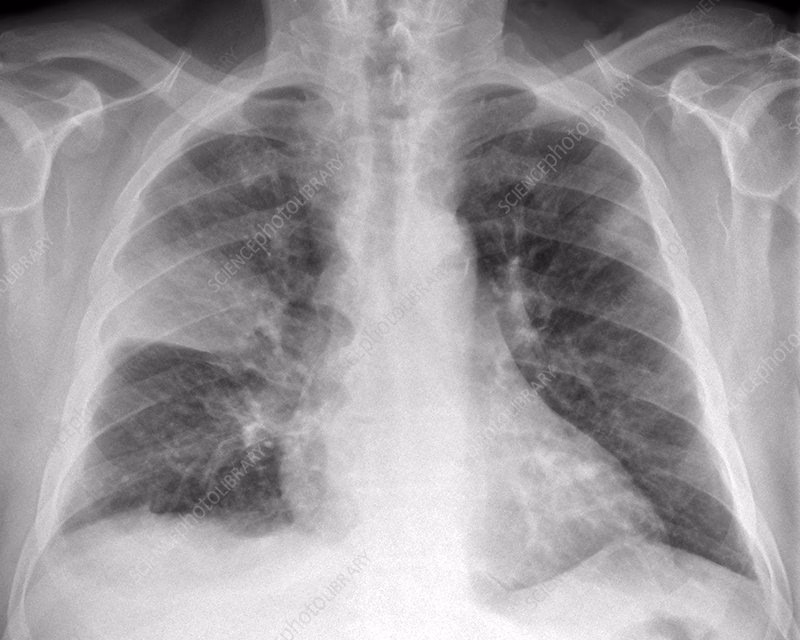

Når en patient henvender sig til lægen med symptomer som hoste, feber, åndenød og brystsmerter, er det primære værktøj til at bekræfte en mistanke om lungebetændelse et røntgenbillede af brystkassen (thoraxrøntgen). Der er flere gode grunde til, at dette er standardproceduren:

- Tilstrækkelig Information: I de fleste ukomplicerede tilfælde kan et røntgenbillede tydeligt vise de klassiske tegn på lungebetændelse, såsom fortætninger (konsolidering) i lungevævet. Det kan fastslå tilstedeværelsen af infektion, vurdere dens omfang og placering.

Et røntgenbillede kan altså i langt de fleste tilfælde give lægen den nødvendige information til at stille en korrekt diagnose og iværksætte den rette antibiotikabehandling.

- Lobar pneumoni: En fortætning, der er afgrænset til en hel lungelap, ses ofte ved klassisk bakteriel lungebetændelse, f.eks. forårsaget af pneumokokker.

- Bronkopneumoni: Pletvise fortætninger spredt i flere områder af lungerne kan tyde på andre bakterielle årsager, som f.eks. Stafylokokker.

- Interstitial pneumoni / Matglasforandringer: Et mere diffust, sløret udseende af lungevævet (kaldet "ground-glass opacities") er ofte forbundet med atypiske bakterier (som Mycoplasma) eller viral lungebetændelse, som f.eks. influenza eller COVID-19.

Det er vigtigt at understrege, at disse mønstre overlapper, og den endelige identifikation af årsagen kræver en kombination af patientens sygehistorie, kliniske symptomer og laboratorieprøver (f.eks. blodprøver, podning fra svælg eller opspyt).